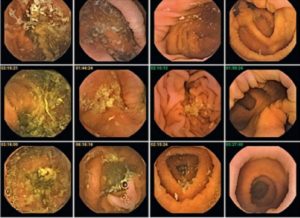

Живот болит изначально приступами, а уже позже приобретает постоянство. У больного можно прощупать пробку в брюшной полости, она может быть как пустая, так и заполненная, что зависит от ее местонахождения. Диагностируют кишечное образование с помощью рентгена.

Потребность в постоянном наблюдении врачей заключается в проведениях ими четких рекомендаций, которые помогут избежать рецидива. При наличии плотных каменных образований в прямой кишке, пациенту потребуется пальцевое исследование или хирургическое вмешательство, основанное на извлечение пробки.